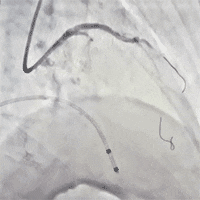

左冠术前造影,重度狭窄伴弥漫性钙化

PCI术后左冠造影